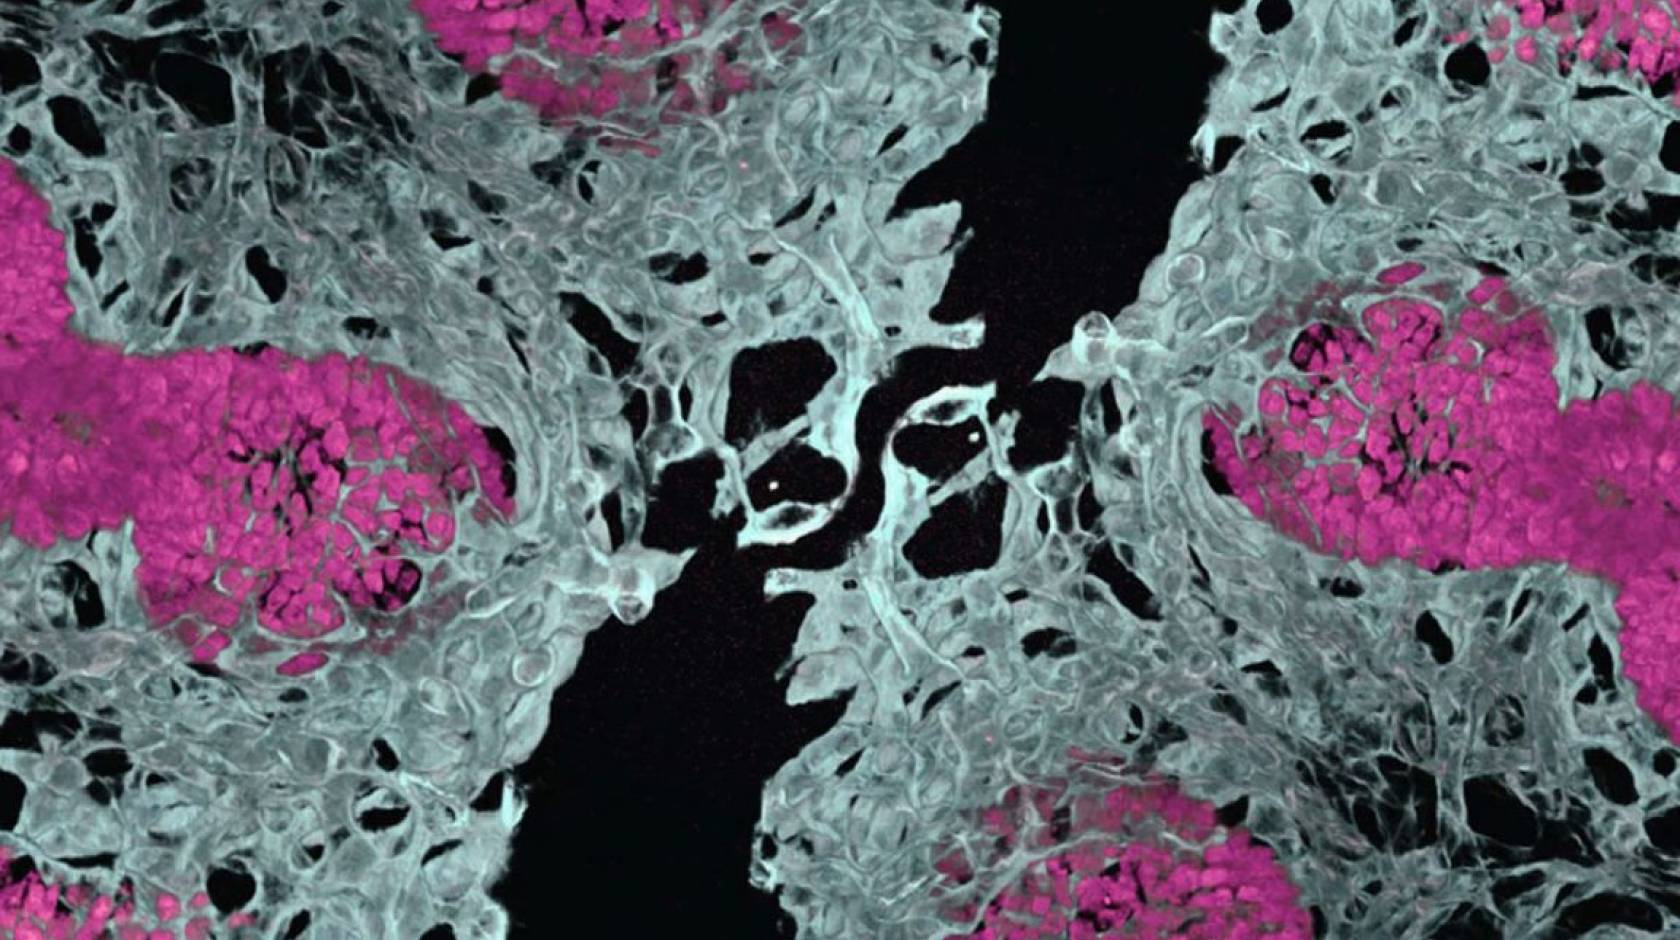

To solve this problem, the team initially tried the conventional assembly approach of growing organ components separately, using fluorescent markers to track different cell types, then combining them at a later stage. Red cells were supposed to become blood vessels, while green cells were meant to become lung tissue.

"We expected red-colored vascular networks and green-colored epithelium," explained Gu, who's also an associate professor of anesthesiology and perioperative medicine at UCLA. "But we actually found red-colored vascular networks and red-colored epithelium, meaning both cell types were surprisingly developing at the same time from the same starting material.”

By allowing lung tissue and blood vessels to grow together from the beginning, the resulting mini-organs demonstrated greater cell type diversity, better three-dimensional structure, improved cell survival and more mature development compared to previous lab-grown organ models.

Using the new method, scientists were able to take stem cells from patients with FOXF1 mutations and grow vascularized lung organoids that recreated both the primary blood vessel defects and the secondary lung tissue abnormalities that result.